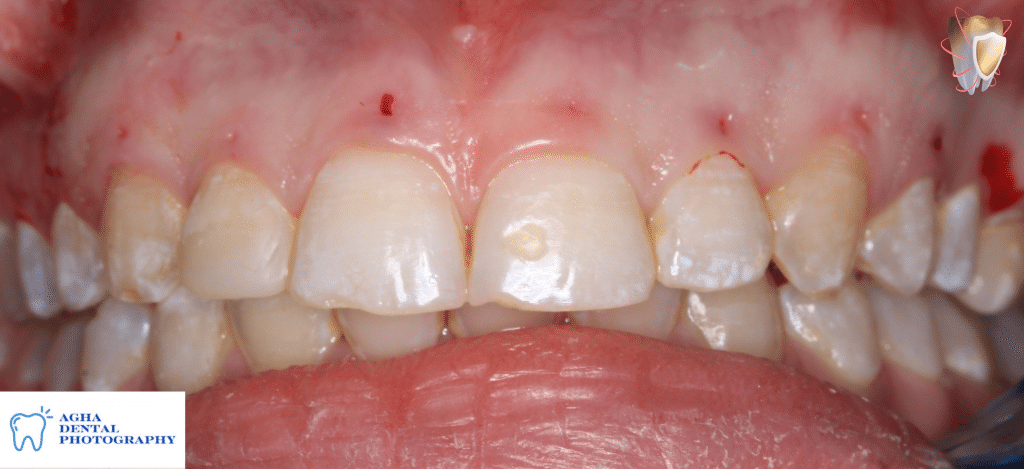

1 month follow up showing correction of gummy smile

Intra oral photo showing harmony of gingival margins

Rechecking the distance during smile after 1 month follow up showing that it was reduced from 4mm to 1mm